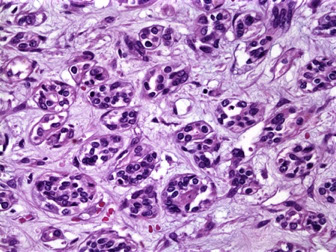

LM: glomeruli enlarged and hypercellular, neutrophils, "lumpy-bumpy" appearance

- nearly every part of every glomerulus affected equally, and should not have features of vasculitis

- glomerular tufts are large and can prolapse into PCT, and usually appear large, solid, and filled c mix of neuts, monos, and swollen cells, and can rarely form crescents

EM: subepithelial immune complex (IC) humps

IF: granular / coarse deposits ("lumpy-bumpy") of C3 and IgG, IgM mainly along the GBM, outside the glomerular capillary loops